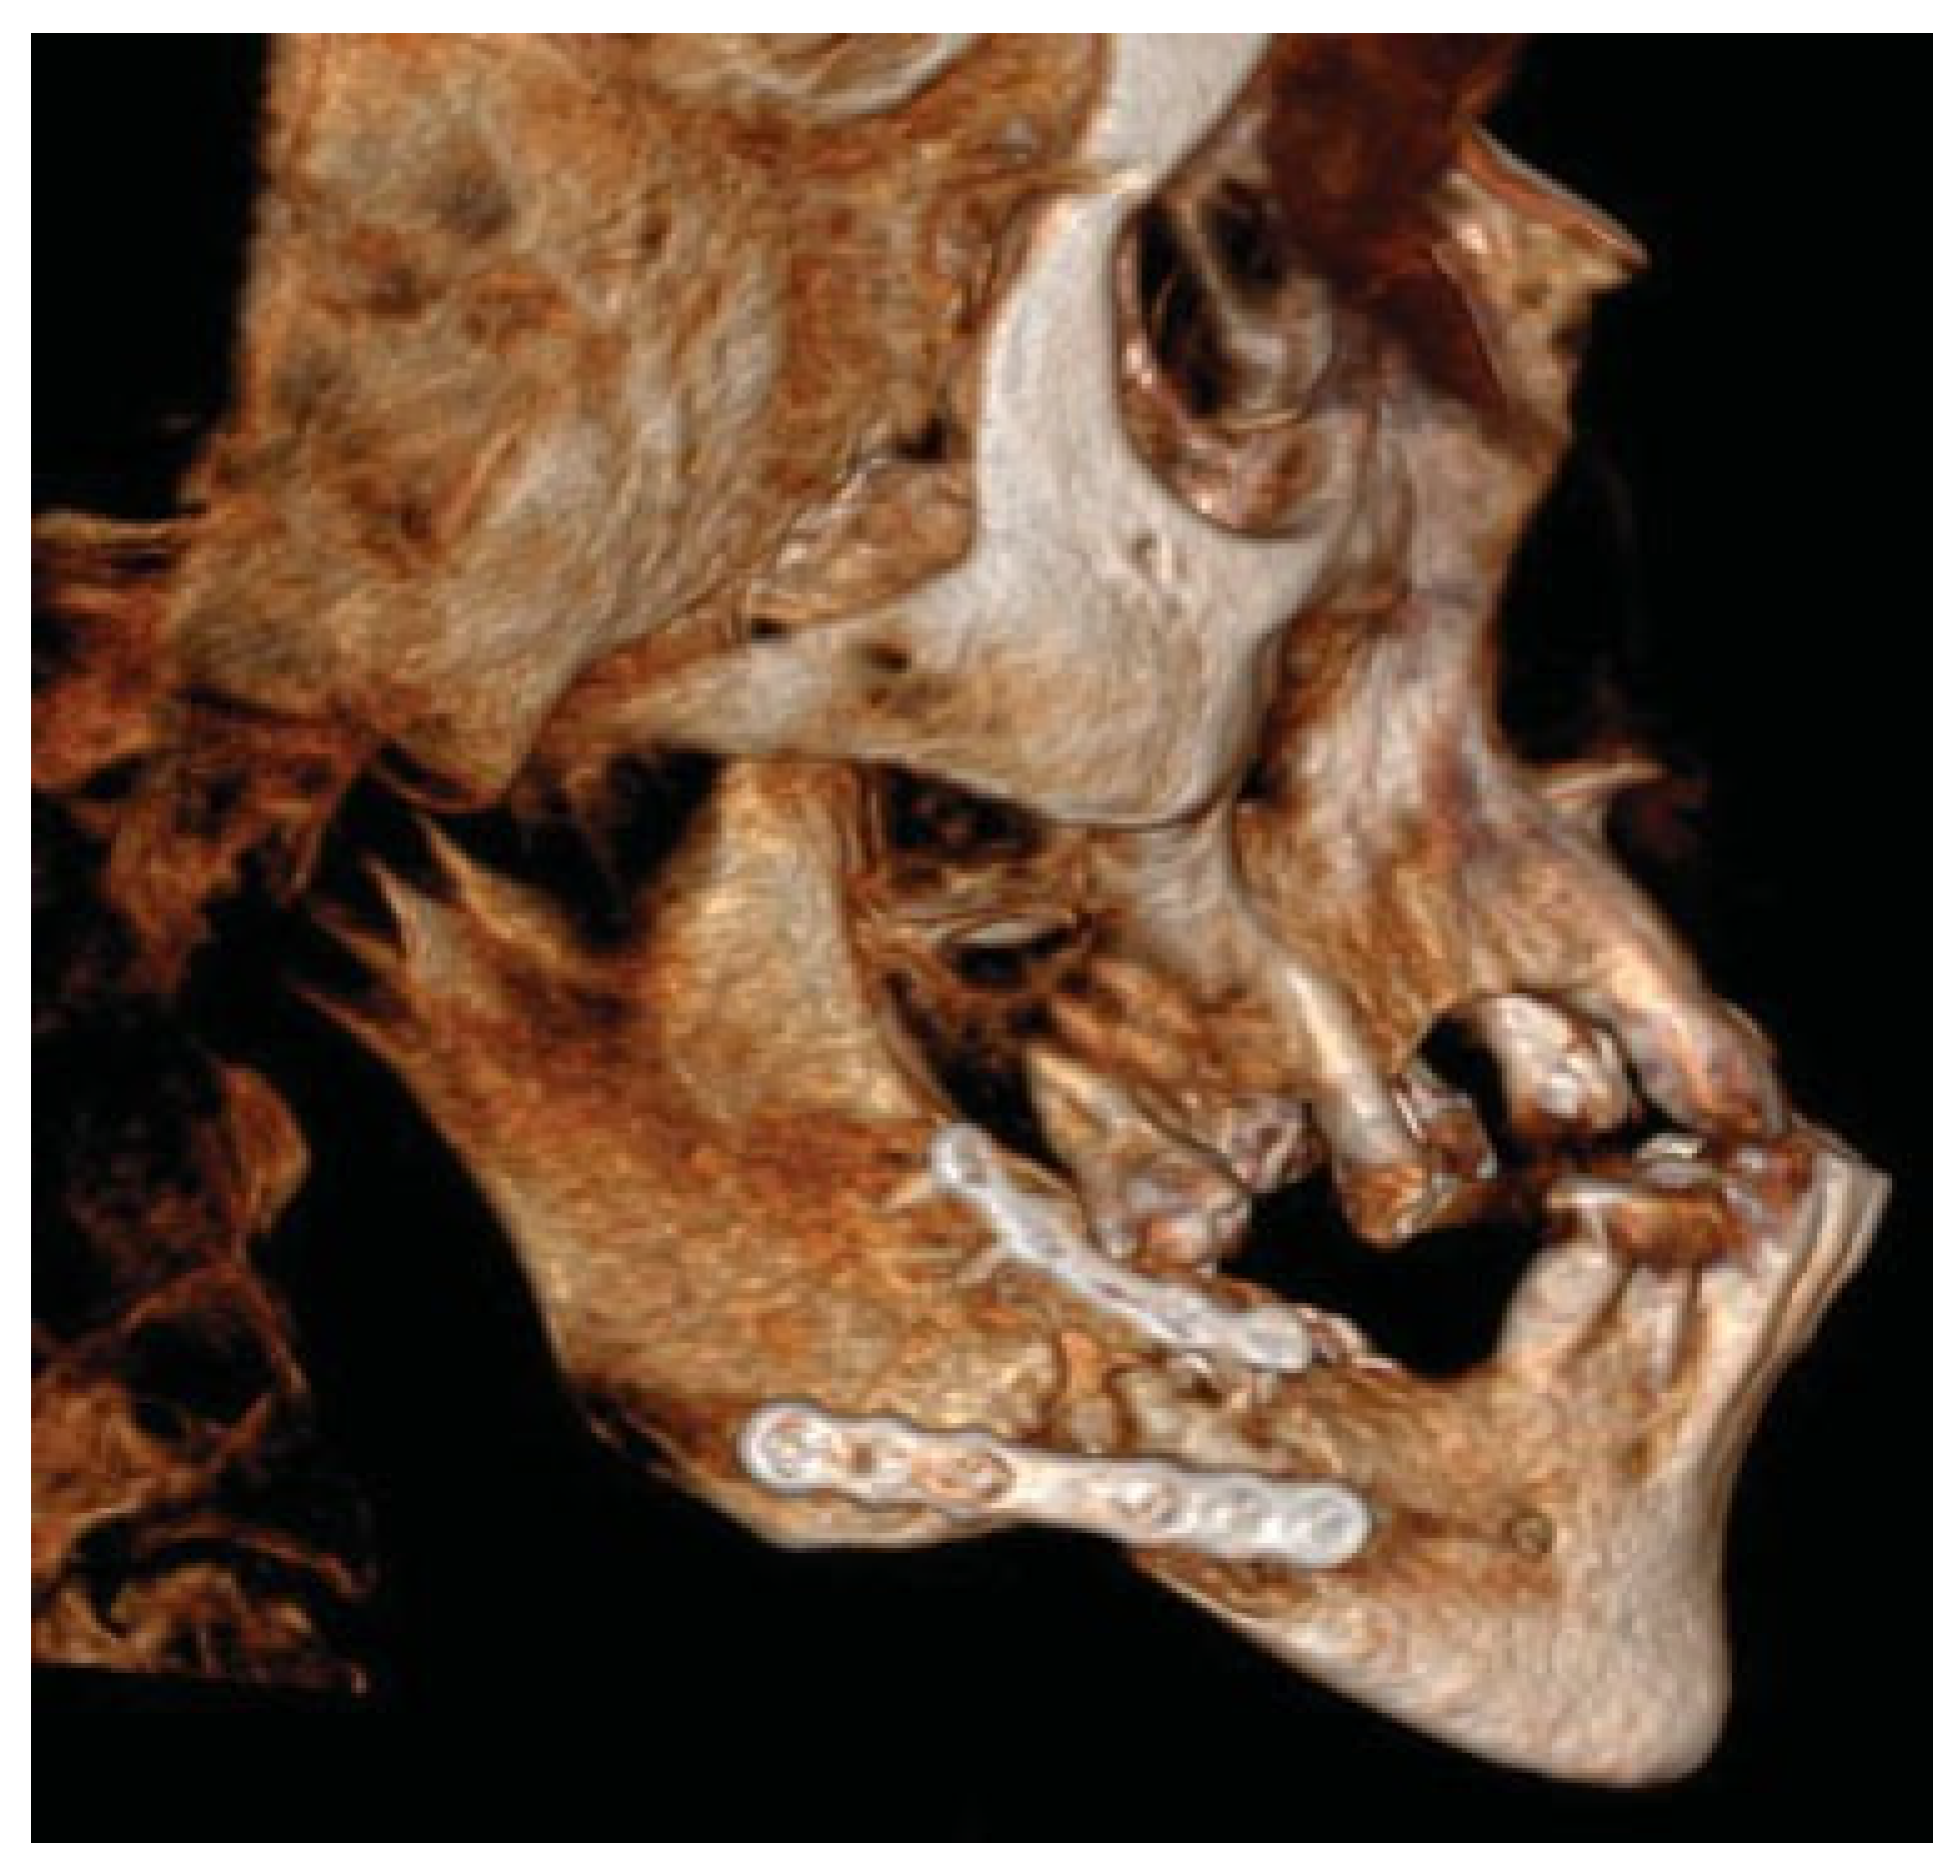

Figure 4.

After plate removal in the software, osteotomies in the fracture areas and corrective rotation of displaced fragments was performed to close the open bite and restore the occlusion in the virtual plan.